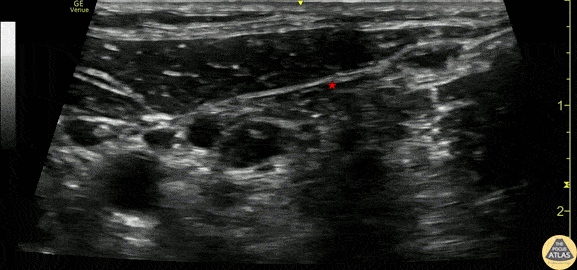

40s F presented to the ED with left shoulder pain after a fall out of bed 1 day prior to arrival. She was found to have a closed, displaced and comminuted fracture of the distal clavicle, which was managed non-operatively with a sling. A superficial cervical plexus nerve block was performed for analgesia. This clip shows the block being performed with an in-plane technique, with the needle entering posteriorly/laterally (screen right), to instill local anesthetic along the fascial plane (*) just deep to the sternocleidomastoid muscle. The carotid artery can be seen pulsating medially (left of screen). The patient had significant improvement of her pain after the block, and was discharged. Drs. Anna Engeln and Matt Riscinti Denver Health Medical Center